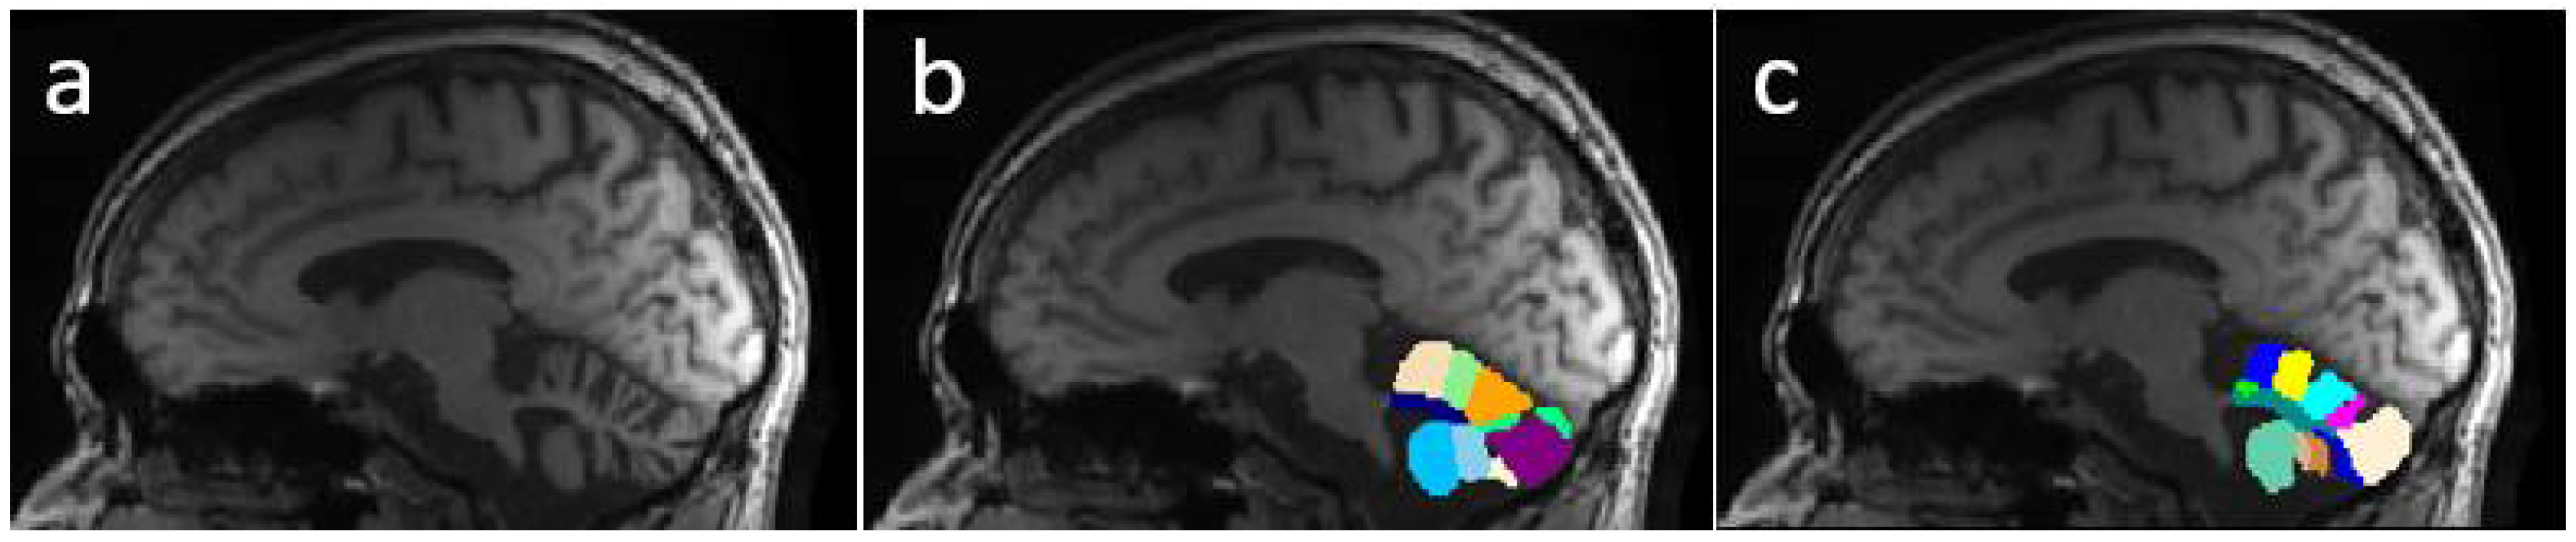

Figure 5 presents an example of segmentation produced by the three models for a subject in our dataset. As the figure shows, ACAPULCO (Figure 5d) only detected parts of the biggest fissures, while the smaller ones are classified as cerebellar tissue. CERES (Figure 5c) recognized fissures better than ACAPULCO, but some of them are also misclassified. Furthermore, some irregularities are present in the front of the cerebellum, leaving some holes in the mask produced by CERES. Segmentations obtained by model M2 (Figure 5b) are very close to the real ones, correctly recognizing most of the fissures.

Figure 6 shows a case of the segmentations produced for this second dataset. As in the previous example, the best segmentations were produced by model M2 (Figure 6b). There are some irregularities on borders, which we think can be corrected by applying some postprocessing technique (rather than longest connected component, which is the only postprocessing we currently apply on segmentations). In this example, ACAPULCO was capable of segmenting some fissures better than CERES (Figure 6c,d).

Figure 5. Example of segmentations produced by the approaches for a sample image from our dataset. Original mask (a), followed by segmentation produced by M2 (b), CERES (c) and ACAPULCO (d).

Figure 6. Segmentations produced by the three approaches for a sample image from the DLBS dataset. Original mask (a), followed by segmentation produced by M2 (b), CERES (c) and ACAPULCO (d).